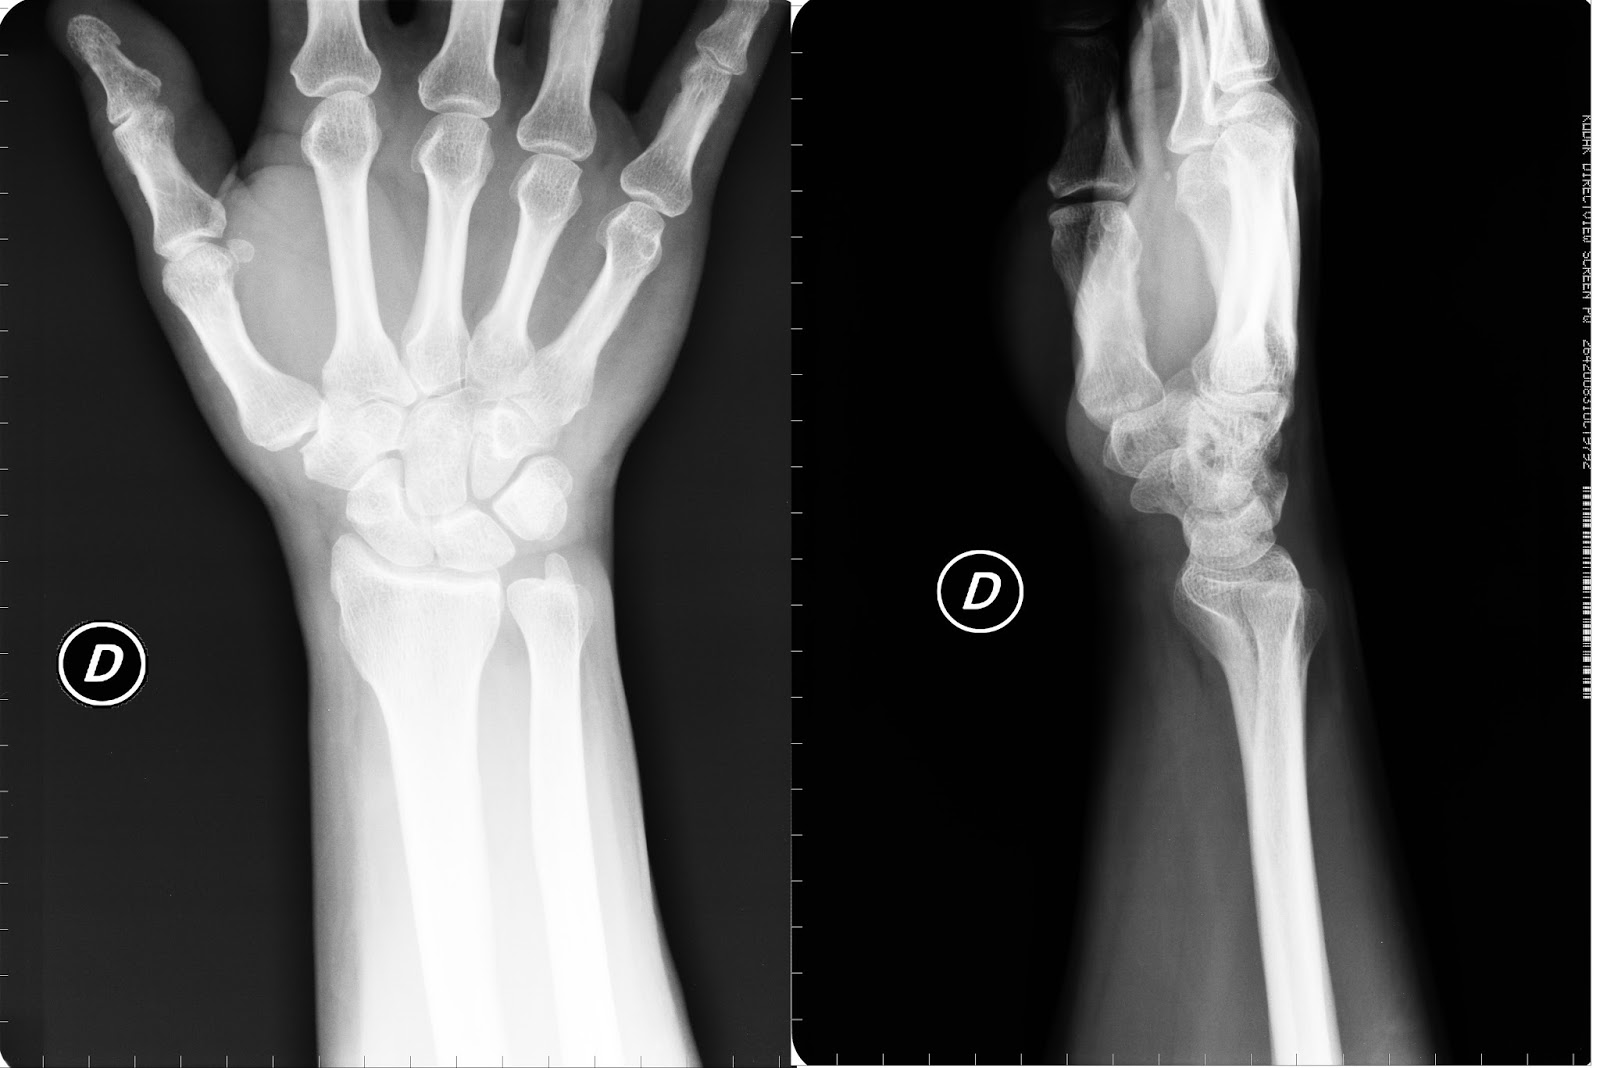

Il polso è composto da otto piccole ossa che si collegano alle due ossa dell'avambraccio lungo chiamate radio e ulna. Nel la classificazione delle fratture di polso non ha scopi puramente accademici;

Questa frattura fu descritta da abraham colles nel 1814 un chirurgo irlandese da qui il nome frattura di colles. Le fratture di polso si suddividono in composte o scomposte, extra articolari o intraarticolari a seconda che la rima di frattura interessi la superficie articolare o meno. Quando sentiamo parlare di polso rotto, l'osso che si rompe più frequentemente è il radio.

Una frattura del polso può determinare rigidità, dolore persistente e/o osteoartrite, soprattutto nei casi in cui si estende all'articolazione del polso o se i frammenti ossei sono dislocati. Il polso è formato dalla parte terminale delle ossa dell'avambraccio: Radio e ulna, inoltre ci sono 8. Il fe si basa sull'applicazioni di 2 viti sul 2° metacarpo (al di sotto della frattura) e 2 viti sul radio (al di sopra della frattura). Distorsione / frattura del polso. La frattura del polso avviene in genere in conseguenza di una caduta a seguito della quale, per evitare il contatto del corpo con il suolo, ci si protegge portando in avanti le mani. La frattura del radio spesso è metafisaria (la metafisica è circa ad 1 cm dall'articolazione) ma potrà interessare anche la superficie articolare. Definizione, ultime notizie, immagini e video dal dizionario medico del corriere della sera. La frattura del polso è la rottura delle ossa dell'avambraccio nella parte più vicina alla mano (distale). Anche se un polso rotto può riferirsi ad una. Una frattura del polso è causata da incidenti e traumi simili a quelli che sfociano in una distorsione. It nell'ultimo anno due lacerazioni, molteplici contusioni e abrasioni, oltre alla recente frattura del polso. Nell'80% dei casi sono interessate le. La frattura del polso è un incidente molto comune favorito dall'attività fisica nel giovane e dall'osteoporosi sebbene nel polso esistano altre ossa che possono lesionarsi, come lo scafoide. Leggi la voce frattura del polso sul dizionario della salute. Fratture in costante incremento per l'aumento della vita media. Le fratture di polso si suddividono in composte o scomposte, extra articolari o intraarticolari a seconda che la rima di frattura interessi la superficie articolare o meno.